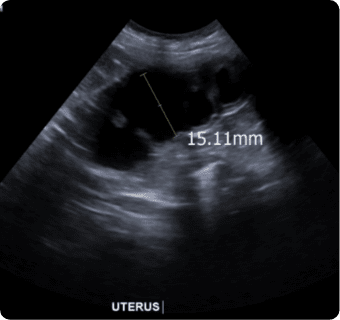

일산시티동물의료센터는 지멘스에서 개발한 고성능 프리미엄 초음파 장비인

Siemens Sequoia를 활용하여 심장, 복부 장기, 림프절 등의 구조물을 선명하게 구현하고,

미세한 해부학적 구조까지 정밀하게 확인할 수 있습니다.

또한 급성 췌장염, 급성 신부전, 자궁축농증, 방광염, 요로결석, 소화기 이물,

비장종양 등의 질환을 진단하고, 환자의 상태를 평가하는 데에도 활용됩니다.